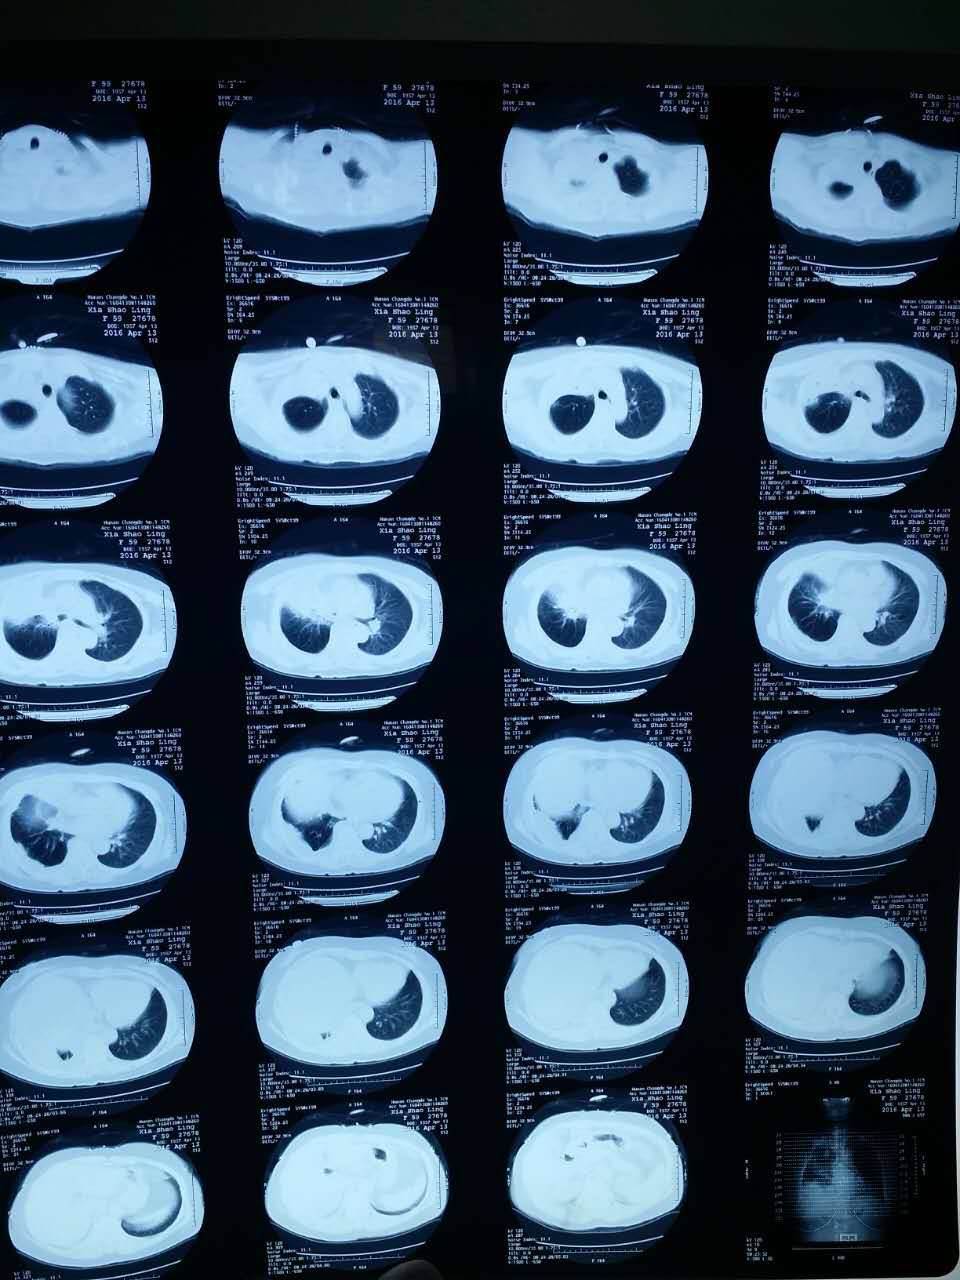

亲们,我妈21突变,今年3月开始吃易瑞沙,胸水减少了,咳嗽少了,最近复查胸水多了,咳嗽厉害了,但是我妈没有脑转,而且我妈的cea之前400多,现在还是三百多,换特罗凯行吗?请问吃特的最佳时间是什么时候?需要吃什么保健品保护内脏吗?